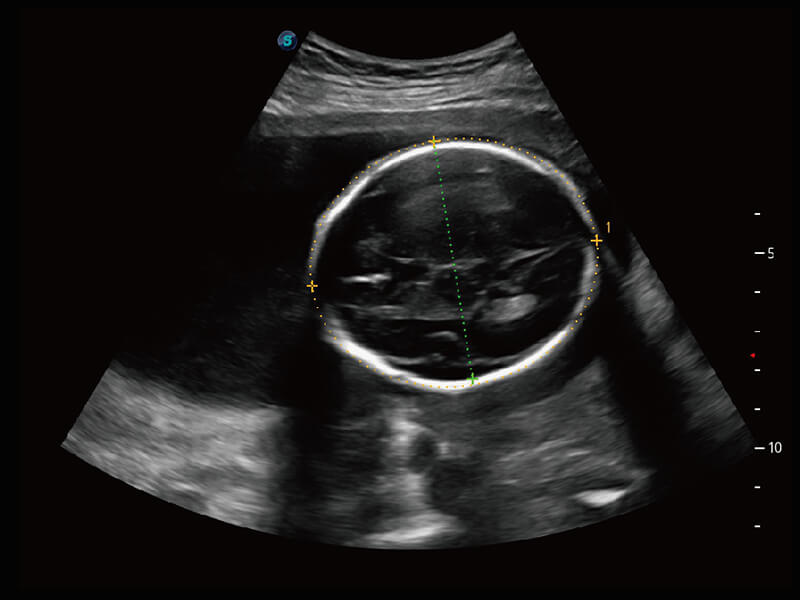

S60探头工艺,从前端信号处理每一个环节采集无损声学数据,真实还原组织原貌,再现解剖细节。

超宽频带技术,为容积成像带来优质的二维图像基础,为您呈现丰富的结构细节,栩栩如生地展示宝宝的宫内形态以及各种组织的立体结构。